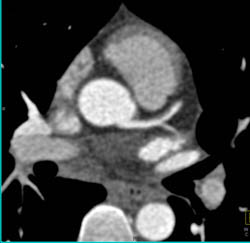

Plaque in LAD